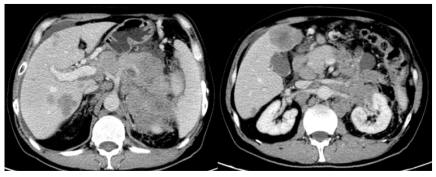

(2023年11月)4周期化疗后,复查CT评效:肝多发转移,较前减少缩小,胰腺区,左肾前,脾内侧多发转移较前明显缩小,肝门区,肠系膜内及腹膜后淋巴结较前明显缩小,部分消失。评效部分缓解(PR)。

image.png

图2 4周期化疗后复查CT结果

(2024年02月)8周期化疗后,复查CT评效:肝多发转移,较前减少缩小,胰腺区,左肾前,脾内侧多发转移较前稍缩小,肝门区,肠系膜内及腹膜后淋巴结较前明显缩小,部分消失。评效维持PR。

图3 8周期化疗后复查CT结果